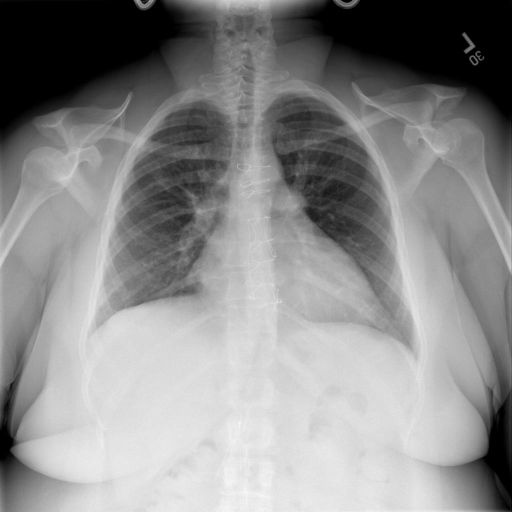

## 本文贡献  - 借助ChatGPT以及公开的数据集,我们构造了一个`X光影像-诊断报告`对的医学多模态数据集; - 我们将构建的中文胸部X光片诊断数据集在[VisualGLM-6B](https://github.com/THUDM/VisualGLM-6B)进行微调训练,并开放了部分训练权重用于学术研究; ## 数据集 - [MIMIC-CXR](https://physionet.org/content/mimic-cxr-jpg/2.0.0/)是一个公开可用的胸部X光片数据集,包括377,110张图像和227,827个相关报告。 - [OpenI](https://openi.nlm.nih.gov/faq#collection)是一个来自印第安纳大学医院的胸部X光片数据集,包括6,459张图像和3,955个报告。 在上述工作中,报告信息都为非结构化的,不利于科学研究。为了生成合理的医学报告,我们对两个数据集进行了预处理,并最终得到了可以用于训练的**英文报告**。除此之外,为了更好的支持中文社区发展,借助ChatGPT的能力,我们将英文报告进行了中文翻译,并最终形成了可用于训练的数据集。 |数据集|数量|下载链接| |:-|:-|:-| |MIMIC-CXR-zh|-|-| |OpenI-zh|6,423|[诊疗报告(英文)](./data/openi-en.json)、[诊疗报告(中文)](./data/Xray/openi-zh.json) 、[X光影像](https://pan.baidu.com/s/13GBsDMKf6xBZBSHpoWH_EA?pwd=k9sh)| ## 快速上手 ### 1.安装环境 ```bash # 安装依赖 pip install -r requirements.txt # 国内换源安装依赖 pip install -i https://mirrors.aliyun.com/pypi/simple/ -r requirements.txt ``` 此时默认会安装`deepspeed`库(支持`sat`库训练),此库对于模型推理并非必要,同时部分`Windows`环境安装此库时会遇到问题。 如果想绕过`deepspeed`安装,我们可以将命令改为: ```bash # 安装依赖 pip install -i https://mirrors.aliyun.com/pypi/simple/ -r requirements_wo_ds.txt # 安装SwissArmyTransformer pip install -i https://mirrors.aliyun.com/pypi/simple/ --no-deps "SwissArmyTransformer>=0.3.6" ``` ### 2.模型推理 |模型权重|下载链接| |:-|:-| |checkpoints-XrayGLM-300|-| |checkpoints-XrayGLM-3000|-| CLI推理: ```python python cli_demo.py --from_pretrained checkpoints/checkpoints-XrayGLM-3000 --prompt_zh '详细描述这张胸部X光片的诊断结果' ``` 更多[参数](https://github.com/WangRongsheng/XrayGLM/blob/main/cli_demo.py#L16) ### 3.模型训练(复现XrayGLM) > 我们所使用的硬件为:四卡A100 80GB - (1)准备[诊疗报告(中文)](./data/Xray/openi-zh.json)和[X光影像](https://pan.baidu.com/s/13GBsDMKf6xBZBSHpoWH_EA?pwd=k9sh)在`data/Xray`文件夹下; - (2)开始训练: ```bash # 设置CUDA变量,主要是为了解决有时候直接训练而出现无法正确加载到显卡问题 export CUDA_VISIBLE_DEVICES=0,1,2,3 # 开始训练 bash finetune_XrayGLM.sh ``` 这里的复现过程非常简单,主要是很多过程我们都为大家准备好了,大家可以随时复现一个自己的`XrayGLM`。 ### 4.模型训练(通用) ## 效果展示 影像诊断: |X光影像|诊疗报告(医生)|XrayGLM| |:-|:-|:-| ||根据X射线图像,心脏大小正常,肺部看起来很清晰。已经排除了肺炎、积液、水肿、气胸、腺病、结节或肿块的存在。该发现表明一切正常。换句话说,总体印象是胸部正常。|X光片显示,心脏大小正常。肺部没有气胸或胸腔积液的证据。骨骼结构看起来没有任何异常。总的来说,X光片表明没有发现急性心肺疾病的迹象。| ||X光图片显示没有扭曲的区域、可疑的骨质不透明度或胸腺积液。心脏大小轻微增大,但非常稳定。此外,没有气胸的证据,肺野也正常。总体来说,X光片显示没有急性心脏异常,但要注意轻微的心脏扩大。|X光片显示,心脏大小正常。肺部和纵隔轮廓清晰,没有气胸或胸腔积液的证据。骨骼结构完整,没有任何急性异常。| ||心影形态在正常范围内。没有急性骨质异常。有可能出现没有明显的吸水或肺实质状况的线索。没有大面积积液或气胸。有可能怀疑其有误吸或肺实质问题。为了确诊和治疗,可能需要进行适当的影像学随访。|心脏大小正常,肺部和纵隔轮廓清晰。没有急性异常或活动受限的证据。没有任何明显的气胸、胸腔积液或肺不张的迹象。此外,也没有发现任何局灶性骨质异常或其他急性疾病。| 多轮对话: |X光影像|诊疗报告(医生)| |:-|:-| ||右侧主动脉突出观察到。心脏大小正常。胸部未发现明显的肺气肿、胸膜积液或可疑的肺部病变。报告指出已知右侧主动脉情况正常。| ```bash >> X光影像路径:./data/Xray/861_1.png >> 用户:这是一张什么图? >> XrayGLM:这张图片显示的是一张肺部检查的X光片。 >> 用户:请描述这张胸部X光片的诊断结果 >> XrayGLM:心脏大小正常,肺部清晰。没有急性心肺疾病的证据。 >> 用户:是否存在肺气肿? >> XrayGLM:没有肺气肿。心脏大小正常,肺部清晰。没有发现急性心肺疾病的证据。 >> 用户:平时饮食该注意什么? >> XrayGLM:饮食应该健康,均衡。建议增加蛋白质的摄入量,因为蛋白质有助于维持肌肉和骨骼的健康。多食用蔬菜、水果、全谷物以及健康的脂肪来源如橄榄油、鱼类等可以帮助获得足够的维生素和矿物质。此外,避免过度饮酒或吸烟,这些习惯可能会对心脏健康产生负面影响。 ``` ## 未来展望 1. 模型的能力更多来源于数据的支持,`OpenI-zh`作为微调数据集,其数据量足以支持研究,在更广泛的任务和性能表现上,我们认为**在大规模数据集上预训练并在高质量少量数据集上微调是一种可行的方案**; 2. 普遍意义的理解上,视觉多模态模型=视觉模型+语言模型。除了需要关注视觉模型信息与语言模型输出的搭配外,还需要**额外关注到语言模型的加强,在人机的对话中,尤其是医疗语言模型的问答上,除了专业的医疗问题回答,带有人文情怀的有温度的回答更应该是我们追寻的目标**。 ## 项目致谢 1. [VisualGLM-6B](https://github.com/THUDM/VisualGLM-6B)为我们提供了基础的代码参考和实现; 2. [MiniGPT-4](https://github.com/Vision-CAIR/MiniGPT-4)为我们这个项目提供了研发思路; 3. ChatGPT生成了高质量的中文版X光检查报告以支持XrayGLM训练; 4. [gpt_academic](https://github.com/binary-husky/gpt_academic)为文档翻译提供了多线程加速; 5. [MedCLIP](https://github.com/RyanWangZf/MedCLIP) 、[BLIP2](https://huggingface.co/docs/transformers/main/model_doc/blip-2) 、[XrayGPT](https://github.com/mbzuai-oryx/XrayGPT) 等工作也有重大的参考意义;  这项工作由[澳门理工大学应用科学学院](https://www.mpu.edu.mo/esca/zh/index.php)硕士生[王荣胜](https://github.com/WangRongsheng) 、[段耀菲](https://github.com/IsBaSO4) 、[李俊蓉](https://github.com/lijunrong0815)完成,指导老师为檀韬副教授、[彭祥佑](http://www.patrickpang.net/)老师。 *特别鸣谢:[USTC-PhD Yongle Luo](https://github.com/kaixindelele) 提供了有3000美金的OpenAI账号,帮助我们完成大量的X光报告翻译工作 ## 免责声明 本项目相关资源仅供学术研究之用,严禁用于商业用途。使用涉及第三方代码的部分时,请严格遵循相应的开源协议。模型生成的内容受模型计算、随机性和量化精度损失等因素影响,本项目无法对其准确性作出保证。即使本项目模型输出符合医学事实,也不能被用作实际医学诊断的依据。对于模型输出的任何内容,本项目不承担任何法律责任,亦不对因使用相关资源和输出结果而可能产生的任何损失承担责任。 ## 项目引用 如果你使用了本项目的模型,数据或者代码,请声明引用: ```bash @misc{wang2023XrayGLM, title={XrayGLM: The first Chinese Medical Multimodal Model that Chest Radiographs Summarization}, author={Rongsheng Wang, Yaofei Duan, Junrong Li, Patrick Pang and Tao Tan}, year={2023}, publisher = {GitHub}, journal = {GitHub repository}, howpublished = {\url{https://github.com/WangRongsheng/XrayGLM}}, } ``` ## 使用许可 此存储库遵循[CC BY-NC-SA](https://creativecommons.org/licenses/by-nc-sa/4.0/) ,请参阅许可条款。